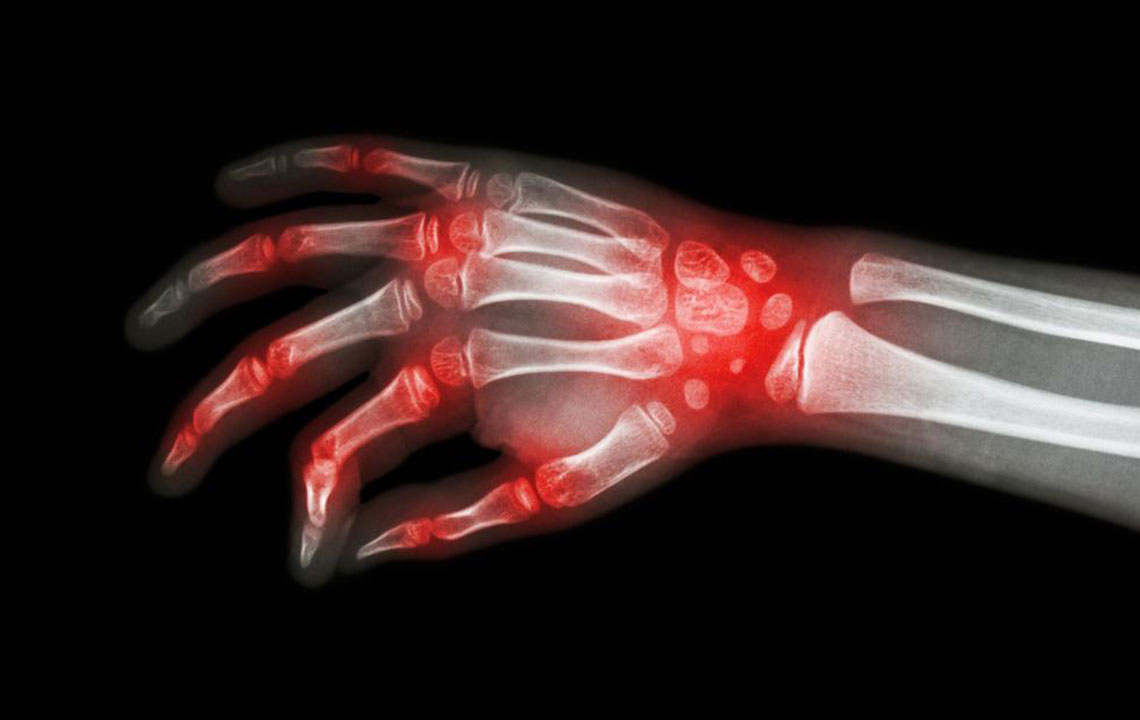

Joint Pain

Stiffness, swelling, and pain are also some of the symptoms indicating the onset of lupus. In most of the cases, pain or swelling associated with lupus is mild in the initial stage and aggravates with each passing day. The pain is not continuous. It comes and goes occasionally. Though the pain can be controlled by taking over-the-counter medicines, it is always better to consult a doctor and seek a complete diagnosis.